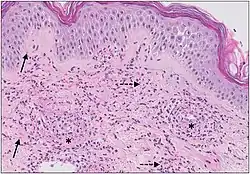

Cutaneous small-vessel vasculitis (CSVV) is inflammation of small blood vessels, usually accompanied by small lumps beneath the skin.[1]: 831 [2] The condition is also known as hypersensitivity vasculitis, cutaneous leukocytoclastic vasculitis, hypersensitivity angiitis, cutaneous leukocytoclastic angiitis, cutaneous necrotizing vasculitis and cutaneous necrotizing venulitis,[3]

It is the most common form of vasculitis seen in clinical practice, usually caused by inflammation of post-capillary venules in the dermis).

"Leukocytoclastic" (literally meaning 'leukocyte-destroying') refers to the damage caused by nuclear debris from infiltrating neutrophils in and around the vessels.[4]

The small vessels in the skin affected are located in the superficial dermis and include arterioles (small arteries carrying blood to capillaries), capillaries, and venules (small veins receiving blood from capillaries).[5] In general, immune complexes deposit in vessel walls leading to activation of the complement system. C3a and C5a, proteins produced from the complement system, attract neutrophils to the vessels.[9] Once activated, neutrophils then release preformed substances, including enzymes, causing damage to vessel tissue.[9] Evidence of this process can be seen with a sample of removed skin tissue, or biopsy, viewed under a microscope. Neutrophils are seen surrounding blood vessels and their debris within vessel walls, causing fibrinoid necrosis. This finding on histological examination is termed "leukocytoclastic vasculitis".[5]